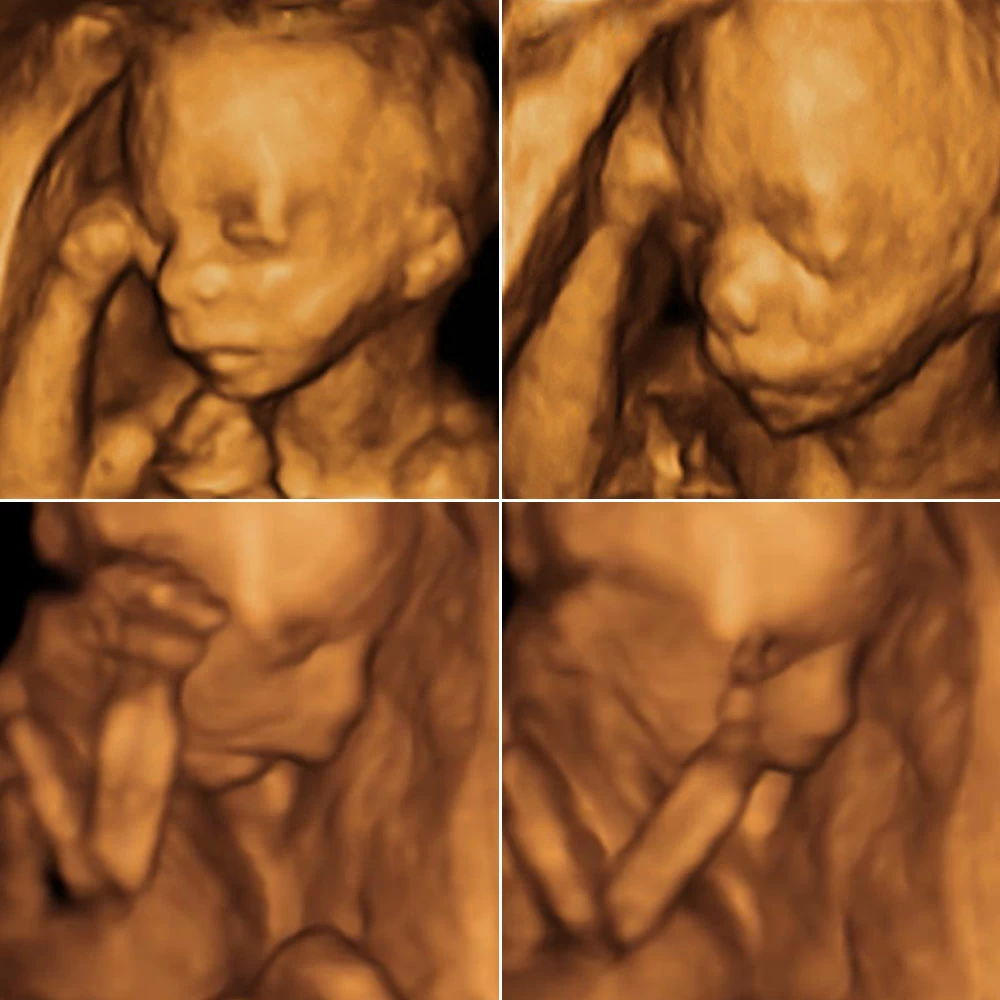

Неделя № 22

На 22 неделе размеры плода увеличиваются до 28 см, вес – до 450-500 грамм. Размеры головки становятся пропорциональны туловищу и конечностям. Ноги практически все время находятся в согнутом состоянии.

Полностью сформирован позвоночник плода: он имеет все позвонки, связки и суставы. Продолжается процесс укрепления костей.

Совершенствуется нервная система плода: головной мозг содержит уже все нервные клетки (нейроны) и имеет массу около 100 грамм. Ребенок начинает интересоваться своим телом: ощупывает свое лицо, руки, ноги, наклоняет голову, подносит пальцы ко рту.